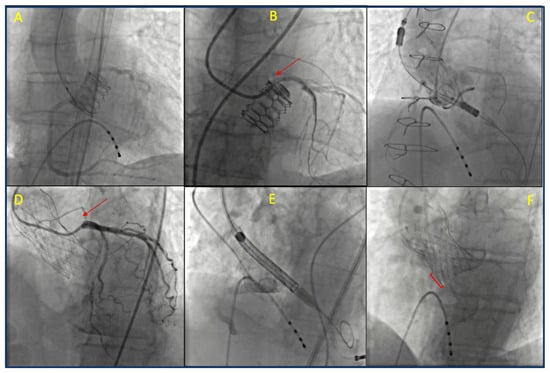

With the expansion of TAVR to include low-risk and younger patients, an increasing number of individuals face the potential risk of requiring future percutaneous procedures to treat coronary or valvular diseases. The lifetime risk of needing unplanned PCI after TAVR is low for patients without CAD at the time of the procedure. However, this risk increases over time for those with pre-existing CAD, particularly in patients with multivessel disease and a high SYNTAX score [86]. Data from the literature and registries indicate that coronary angiography and PCI may be necessary for nearly 2% of patients undergoing TAVR within the first year and for 16% within five years post-TAVR. Moreover, approximately two-thirds of these procedures are performed in the context of acute coronary syndromes, mainly unstable angina or NSTEMI [87,88]. Additionally, younger patients are considered a high-risk group due to their longer life expectancy, as are those with multiple CAD risk factors and those who have a history of PCI [89,90]. Given this context, it is essential to carefully plan the initial valve procedure, while also considering anatomical and technical factors that may affect the success and prognosis of any future procedures. Ensuring the possibility of coronary re-access after TAVR is a critical consideration in this planning process. Angiographic visualization of transcatheter aortic valve replacement periprocedural images and their spatial relationship with the coronary arteries are reported in Figure 3.

Post-TAVR coronary cannulation can be difficult due to subsequent structural modifications caused by the presence of the THV prosthesis that may lead to coronary obstruction or displacement of coronary ostia. Achieving successful coronary access is particularly challenging with older generations of valves, in centers without TAVR experience, or for operators with limited expertise. We propose a detailed algorithm we believe to be helpful for coronary cannulation following TAVR (Figure 5). Cannulation is generally easier with BEVs due to their sub-coronary positioning compared to that of SEVs [107]. As previously discussed, the difficulty of engaging the coronary ostia depends on various anatomical and technical factors. These include the anatomy of the aortic root and STJ, the dimensions of the sinuses, the height and location of coronary artery take-offs, the design and positioning of THVs, and the alignment of the valve’s commissures [6]. This latter issue is crucial, since misalignment can interfere with accessing the ostia, increasing the risk of procedural complications [6]. In this context, a comprehensive pre-procedural imaging strategy, including contrast-enhanced CT scans, can assist in planning coronary access in non-acute situations.

A CT scan evaluates the aortic root, valve characteristics, and the relationship between the coronary ostia and the THV, identifying any potential obstacles such as valve frames, thrombosis, or calcifications [115]. It can also provide details on vascular access options. If a CT scan is unavailable, due to factors like chronic kidney disease or the risk of procedure delays, if the TAVR procedure was performed at the same center, reviewing clips from previous procedures can offer valuable insights regarding anatomical alignment, valve depth, and coronary take-off positions. In the absence of prior clips, an aortogram should be performed, typically using a left oblique view or a right caudal view for certain SEVs like the Evolute valve. Moreover, choosing the most familiar vascular access for the operator is crucial, keeping in mind both valve characteristics and the anatomical configuration of the vessels. For instance, access through tortuous brachiocephalic vessels should be avoided. The right radial artery remains the preferred access for most operators in everyday cath lab procedures, although its use in post-TAVR patients has not been extensively studied. Most previous studies on coronary re-access in TAVR patients have been conducted using femoral access [104,107,116]. An alternative to femoral access is left radial artery access, which may reduce catheter manipulation and improve angulation for selective coronary cannulation. Moreover, studies suggest that selective engagement of the coronary ostia might be more successful by employing additional techniques, such as using a coronary guidewire or guide-extension catheter, particularly when using radial access [104,107].

As previously noted, the type of valve can significantly influence catheter selection and procedural steps. For patients with BEVs, standard diagnostic catheters could be used without modification just by positioning them over the superior edge of the valve frame. In some instances, a hydrophilic guidewire can be carefully advanced under fluoroscopy to avoid damaging the valve, or a buddy wire may be used for additional support. In contrast, SEVs, especially when misaligned, complicate coronary cannulation. Procedural failures may occur due to difficulties in crossing the valve struts or incorrect placement within the coronary artery resulting from inadequate catheter support [87]. Yudi et al. proposed a catheter selection strategy based on the type of THV, the specific procedure being performed (coronary angiography or PCI), and the relationship between the transcatheter commissural post and the coronary ostium. In challenging cannulation scenarios involving BEVs, especially when a commissural tab obstructs the coronary ostium—non-selective angiography may be sufficient. Alternatively, a guidewire “fishing” technique, followed by the positioning of the guide catheter, or the use of catheter extensions can also be effective. In rare cases of high BEV deployment, a multipurpose catheter may facilitate engagement [94].